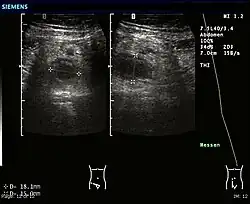

Ultrasound

Abdominal ultrasonography, preferably with doppler sonography, is useful to detect appendicitis, especially in children. Ultrasound can show the free fluid collection in the right iliac fossa, along with a visible appendix with increased blood flow when using color Doppler, and noncompressibility of the appendix, as it is essentially a walled-off abscess. Other secondary sonographic signs of acute appendicitis include the presence of echogenic mesenteric fat surrounding the appendix and the acoustic shadowing of an appendicolith.[59] In some cases (approximately 5%),[60] ultrasonography of the iliac fossa does not reveal any abnormalities despite the presence of appendicitis. This false-negative finding is especially true of early appendicitis before the appendix has become significantly distended. Also, false-negative findings are more common in adults where larger amounts of fat and bowel gas make visualizing the appendix technically difficult. Despite these limitations, sonographic imaging with experienced hands can often distinguish between appendicitis and other diseases with similar symptoms. Some of these conditions include inflammation of lymph nodes near the appendix or pain originating from other pelvic organs such as the ovaries or Fallopian tubes. Ultrasounds may be either done by the radiology department or by the emergency physician.[61]

Ultrasound showing appendicitis and an appendicolith.[62]

Ultrasound showing appendicitis and an appendicolith.[62] -

Ultrasound of a normal appendix for comparison. -

A normal appendix without and with compression. Absence of compressibility indicates appendicitis.[59]